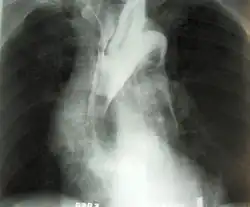

W rozpoznaniu wykonuje się badania obrazowe. Rtg klatki piersiowej, USG, tomografia komputerowa (TK), rezonans magnetyczny (MRT) są badaniami z wyboru. Stosowana jest również angiografia[1].